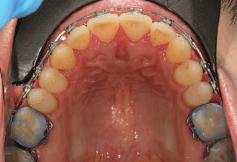

7Dental Tribune Bulgarian Edition / октомври 2022 г. Преди лечението Фиг. 1 Фиг. 4 Фиг. 7 Фиг. 10 Фиг. 13 Фиг. 16 Фиг. 17 Фиг. 18 Фиг. 19 Фиг. 20 Фиг. 11 Фиг. 14 Фиг. 12 Фиг. 15 Фиг. 8 Фиг. 9 Фиг. 5 Фиг. 6 Фиг. 2 Фиг. 3

8 Dental Tribune Bulgarian Edition / октомври 2022 г. По време на лечението Фиг. 21 Фиг. 25 Фиг. 30 Фиг. 31 Фиг. 34 Фиг. 38 Фиг. 40 Фиг. 44 Фиг. 48 Фиг. 50 Фиг. 49 Фиг. 46 Фиг. 39 Фиг. 41 Фиг. 45 Фиг. 47 Фиг. 42 Фиг. 43 Фиг. 35 Фиг. 36 Фиг. 37 Фиг. 32 Фиг. 33 Фиг. 26 Фиг. 28 Фиг. 29 Фиг. 27 Фиг. 22 Фиг. 23 Фиг. 24

9Dental Tribune Bulgarian Edition / октомври 2022 г. След лечението За авторите: Д-р Манол Ивчев е създател на COLDY DENT Functional Atelier, завършва дентална медицина във ФДМ, София. Шест години е стажант в ортодонтска практика. Интересите му са изцяло насочени към функционалната дентална медицина. Посещава курсовете на Доусън и Льо Гал. Преминава редица обучения, акредитирани от Института на Славичек във Виена – VieSID. Впоследствие става най-младият инструктор във VieSID. Придобива права да преподава философията на проф. Рудолф Славичек в България. В практиката си се придържа към протоколите на Славичек за функционално лече ние и диагностика, тъй като те са насочени към комплексно лечение. Завършва всички нива за морфология на зъбите и моделаж при Janos Mako. Повишава знанията си по функционална ортодонтия чрез индивидуален курс в Румъния. Д-р Ивчев е и сертифициран зъболекар по лингвална ортодонтия от Катедрата по ортодонтия от Университета по стоматология в Тегу, Южна Корея. Сертифициран е и за лечение на ортодонтски аномалии чрез миофункционални апарати, а също и за ортодонтия, подпомагана от миниимпланти, отново от Университета по стоматология в Южна Корея. Завършва индивидуално обучение по функционална ортодонтия в Университета по дентална медицина в Богота, Колумбия, както и индивидуално обучение по функционална ортодонтия и физиотерапия по про токола на Mariano Rocabado. Има завършено индивидуално обучение по функционална зъботехника и функционален Wax-Up клас I,II и III. Завършва курс за Digital Smile Design и Skin Concept в Люксембург при Christian Coachman, Florin Cofar, Paulo Kano, Josef Kunkela, Livio Yoshinagа. Зт. Leandro Gambogi, Бразилия, завършва зъботехника през 1999 г. Експерт и пионер в дигиталната диагностика. Лектор и инструктор на курсове в областта на дигиталното протезиране. Понастоящем е главен изпълнителен директор и зъботехник в DENTALE DIGITAL LAB. В периода януари 2005 г. – декември 2006 г. завършва бизнес управление и администрация в Methodist University Center Izabela Hendrix. Съавтор на книгата Odontologia Digital: Desafiando os Limites, глава 5: „Дигитално включване във времето. Технология CAD/CAM“. Преминал множество обучения при световноизвестни кли ницисти. Фиг. 51 Фиг. 54 Фиг. 57 Фиг. 58 Фиг. 63 Фиг. 64 Фиг. 65 Фиг. 59 Фиг. 61 Фиг. 62 Фиг. 60 Фиг. 55 Фиг. 56 Фиг. 52 Фиг. 53 Фиг. 66